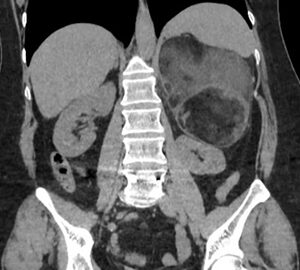

Pte femenino de 52 años, Mc: dolor abdominal difuso, App: hta, Mh: Losartan, A qx: osteosíntesis lumbar.